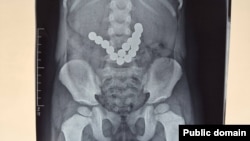

Баланын ичиндеги магнит.

Ошто оюнчуктун 17 магнитин жутуп алган эки жашар балага операция жасалды. Ош облус аралык балдардын клиникалык ооруканасынан билдиришкендей, баланын жакындары ал үч күндөн бери кусуп жатканын айтып райондук ооруканага кайрылган. Рентгенден текшерүүнүн жыйынтыгында ичегилерде бир нече тизилген белгисиз зат аныкталган.

Оорукананын хирургдары балага тез арада операция жасап, жутулган 17 даана магнитти ичегилеринен алып чыгышкан. Ушул тапта баланын абалы туруктуу деп бааланууда.